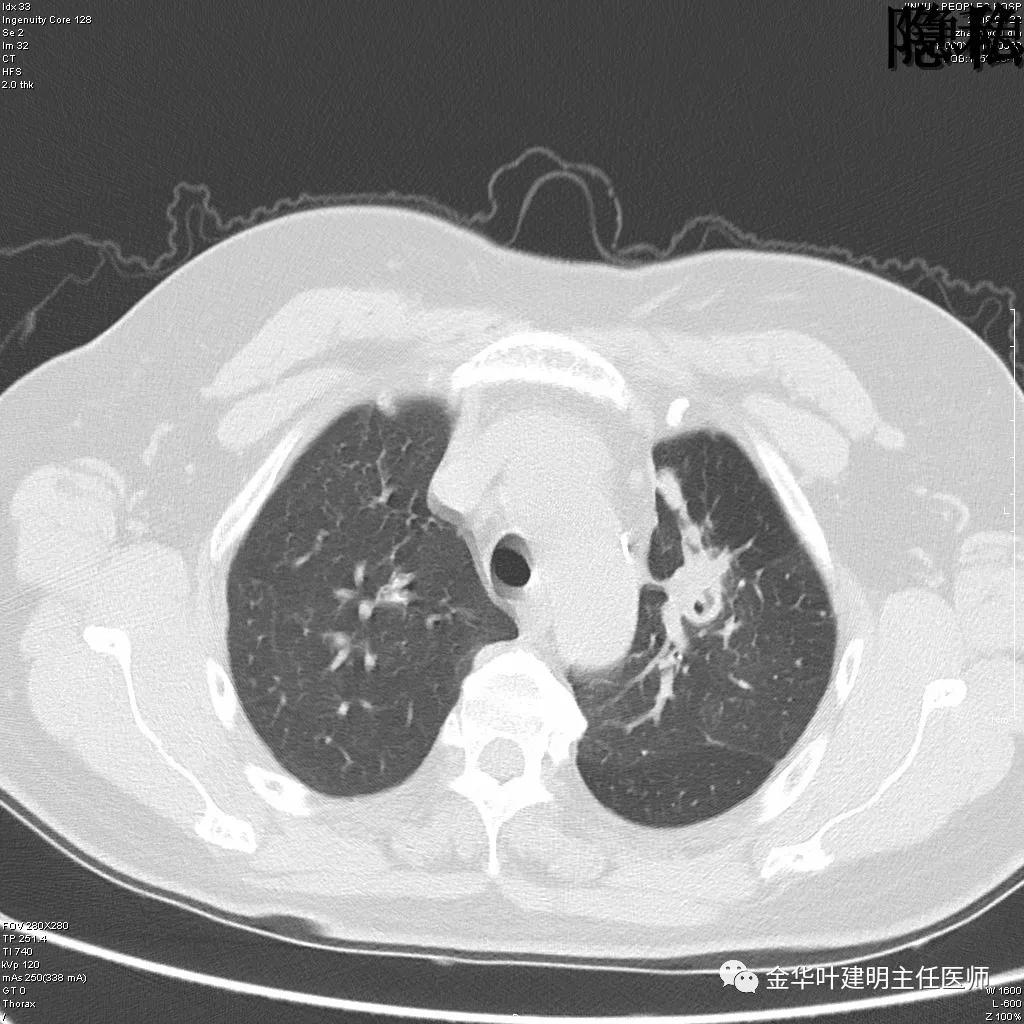

(病例资料2019年)金华的章某,今年60岁,前段时间因为咳嗽,到市区某三甲医院检查,发现她的左肺上叶与左肺下叶都有占位性病变。由于章某有亲戚在我们医院工作,所以在亲戚的指引下,让她来找我。我们予以适当的抗炎治疗,然后复发CT,发现病灶没有任何变化。其中平扫的片子如下:

可见左肺上叶有一占位,是空腔性的,其内有实性密度填充,是比较典型的肺曲菌病的表现,但病灶有点大,长径大于3-4厘米许。

可见左肺下叶比较靠中央的部位也有一病灶,是混合磨玻璃影,偏实性,瘤肺边界清楚,是较为典型的肺癌表现。进一步的靶扫描图像如下: